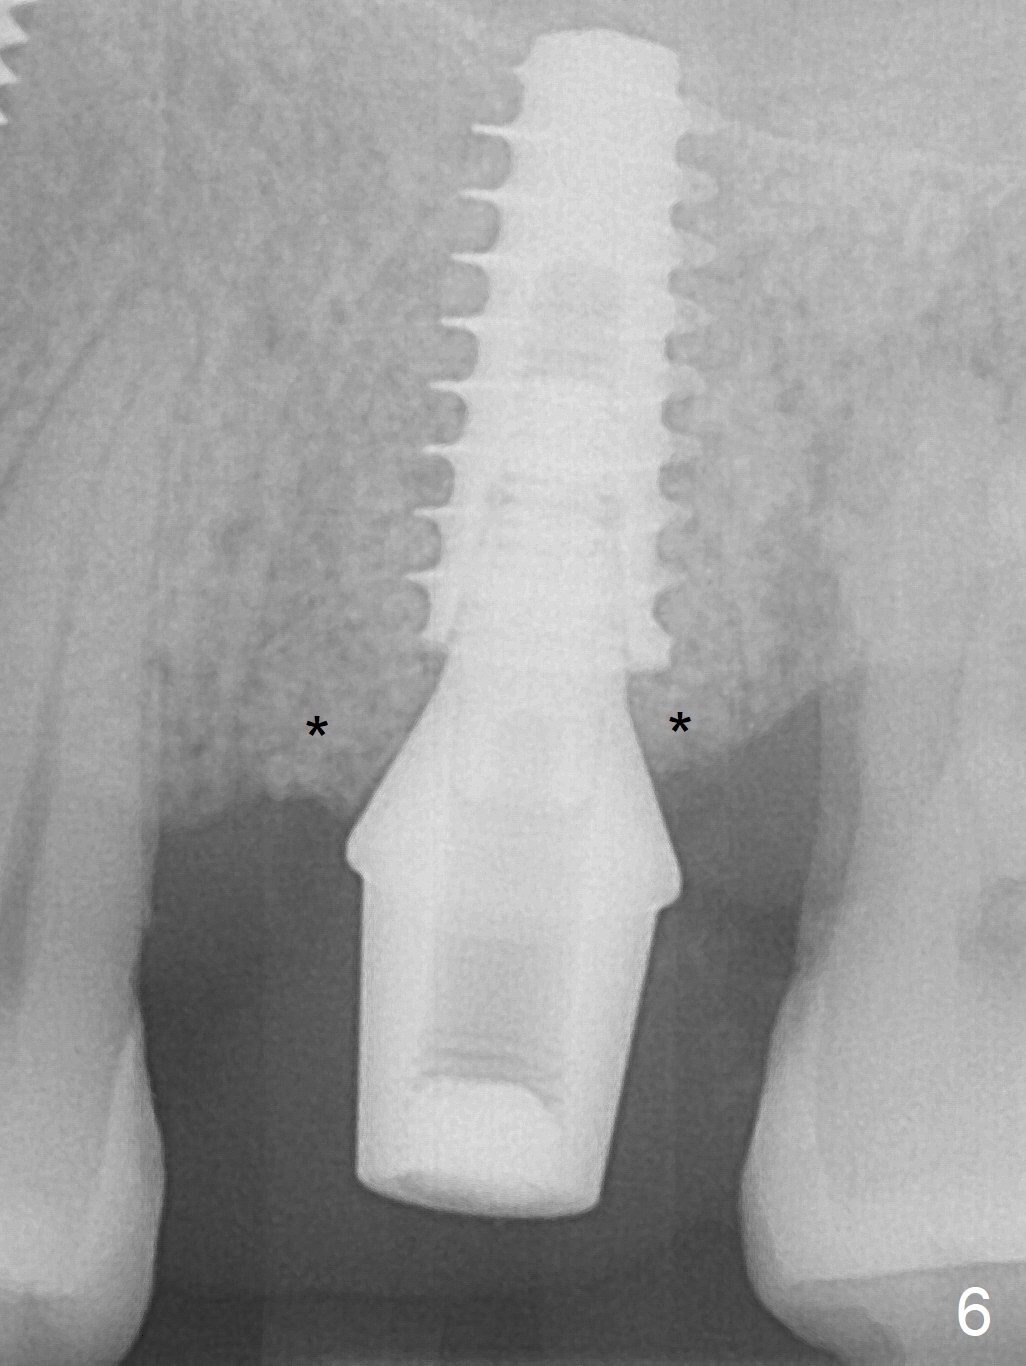

The ridge over the mobile tooth #14 is wide, suggesting bruxism pathogenesis (Fig.1). In spite of calculus over the roots of the extracted tooth (Fig.2), the septum remains. Osteotomy is initiated in the palatal slope of the septum (Fig.3,3' red dashed line). A 4.3 mm Magic Drill (MD) cannot bite into the bone probably because of the slope. Sequential osteotomy has to be done, starting with the smallest MD until 4.8 mm one. A 5x9 mm dummy implant is placed with 50 Ncm (Fig.4). To place 5x11 mm IBS implant (Fig.5), 5.3 mm MD has to be used; prior to implant placement, sinus lift is accomplished with mixture of autogenous bone and Vanilla graft (white *); more allograft (black *) is placed around the implant before insertion of a 6x5.7(3) mm abutment. More allograft is placed around the abutment (Fig.6 *) prior to an immediate provisional fabrication. The grafted bone appears to become the native bone, although at the low density, 6.5 months postop (Fig.7). The implant at #14 appears to have been placed in the middle of the alveolus buccopalatally (Fig.8).